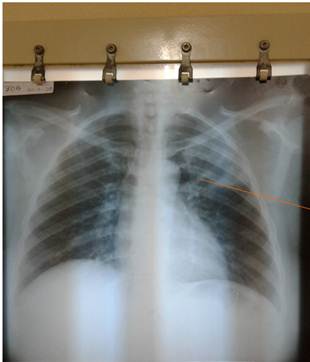

Procederes diagnósticos específicos se realizó radiografía simple de tórax antero-posterior y basiloscopia. La radiografía mostró en el lóbulo superior izquierdo una imagen cavitaria radiotransparente de aproximadamente 4 cm, con lesiones inflamatorias asociadas extendidas hasta el cuerpo superior del hilio (signo de la raqueta de tenis o punta de flecha). Por ello se planteó tuberculosis pulmonar (Fig. 1). Baciloscopia: Esputo BAAR 1: codificación 9.

La exploración mediante Rayos X constituye un método de diagnóstico irreemplazable que se debe utilizar cuando de este estudio dependen decisiones terapéuticas. Para cada región a examinar existen técnicas y proyecciones precisas. En los estudios radiográficos del tórax se precisa la presencia de imágenes cavitarias, las cuales tienen entre sus principales etiologías las cavernas tuberculosas, el absceso del pulmón y el cáncer ulcerado. De acuerdo a sus características será su interpretación. Las cavernas tuberculosas se encuentran sobre todo a nivel de los vértices. Sus paredes pueden ser delgadas o gruesas, únicas o aisladas o, por el contrario, múltiples. Se asientan en parénquima sano o en el seno de un infiltrado.1) Alves y Póvoas recientemente publicaron el caso de una niña angolana con imagen radiológica compatible con TB pulmonar, pero que revela cavitación extensa apical en ambos pulmones, adyacente a los bronquios de drenaje (signo de la raqueta de tenis o punta de flecha).10

La imagen radiográfica cavitaria extendida, también conocida como signo de la raqueta de tenis o punta de flecha, no se observa con frecuencia en el diagnóstico en la APS. En dicho contexto, un enfoque integral está dirigido a detectar y modificar factores de riesgo. En este caso en particular, se consideró, en primer lugar, el antecedente de familiares de primer grado de consanguinidad con la enfermedad, con quienes convivió durante años la paciente. Otro factor importante fue el antecedente de diabetes mellitus e hipertensión arterial.